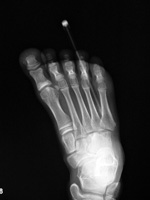

| Nail in foot |

| Young man wearing sandals stepped on a nail. The nail penetrated his plantar soft tissues but this radiograph showed it had not entered bone. From Hunter, 1994 |